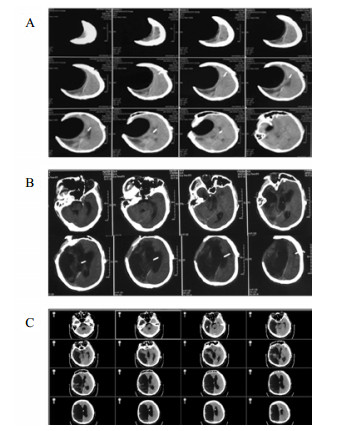

将分流管压力降为0.5后的第6天,该患者复查头颅CT和意识水平均无明显改变;后经分流储液囊穿刺脑脊液外引流,每日引流量150 mL,持续10 d,仍无明显改变。再将脑脊液外引流量增至300 mL/d,患者行为学稍有变化,开始出现刺激后头部转动、手部摸索活动,眼球能视觉追踪。复查头颅CT示脑室形态略缩小。因此,在此基础上再次手术将分流管由原来的抗虹吸可调压管更换为非抗虹吸可调压管,压力设为1.0。患者意识水平进一步改善,术后第4天复查CT示脑室较前缩小(图 2),其大小形态接近正常。随访一年,患者生活能自理,E-GOS 5分。

| 图 2 病例1更换分流管后第4天头颅CT |

入院后于2017年10月30日行“颅骨修补+V-P分流术”。术后将分流管压力逐步调至0.5。患者术后意识无明显改善,复查CT示脑室仍显著扩大。观察2周后病情同前,遂将储液囊外接引流,每日引流量约200 mL,持续3 d,未见行为学及影像学明显变化。加大引流至每日300 mL,持续3 d后,患者自主睁眼增多;引流量增至每天400 mL左右,患者能呼唤下睁眼和视觉追踪。而停止脑脊液外引流后,患者则退步到引流前水平。决定通过按压储液囊促进脑脊液引流(按压600次/d),持续10 d后,睁眼时间延长但仍无意识。考虑到患者意识水平和引流量明显相关,增加按压储液囊频率至1 500次/d,患者又能呼唤睁眼,但CT未见脑室明显缩小。随后增加按压至2 000次/d时,偶尔能出现遵嘱活动,复查CT示脑室结构较前稍有缩小,但脑室仍显扩张。动态观察患者的行为学变化和反复CT随访,逐步升至4 000次/d,患者可表达简短言语,但脑室仍略扩大。随后每月按压次数递增1 000次直至6 000次,复查CT示脑室结构明显缩小(图 4A);患者意识显著改善,能简短正确对答。2018年6月病情稳定后,逐渐减少到3 000次/d, 并复查头颅CT(图 4B)。患者意识完全恢复,交流言语思路清晰,搀扶能行走。

| A:2018年3月27日头颅CT,此时6 000次/d,脑室系统明显缩小;B:2018年9月15日头颅CT,3 000次/d 图 4 病例2头颅CT |

病例4,男,26岁,因“车祸致颅脑损伤昏迷6个月”而入我院。急诊行开颅血肿清除术后1个月因脑积水而行V-P分流术。入院体检:GCS 7分,植物状态,四肢肌张力高,双巴氏征阳性。入院诊断为:重型颅脑损伤术后,脑积水V-P分流术后,持续性植物状态(图 6A)。考虑V-P分流过度引流,将分流调压阀调至最高的2.5水平,骨窗压力和头颅CT没有明显改变。遂将分流管皮下缝扎完全阻断,骨窗压力逐渐升高,术后复查CT(图 6B), 同时患者意识水平改善至微小意识状态。因脑积水加重再行V-P分流术,并择期予右额颞颅骨修补重建,随访头颅CT见图 6C。随后患者恢复至GCS 15分。

| A:男,26岁,颅脑损伤术后6个月入院时头颅CT;B:2015年1月4日分流管缝扎后CT;C:2017年3月8日V-P分流和颅骨修补术后 图 6 病例4 CT |